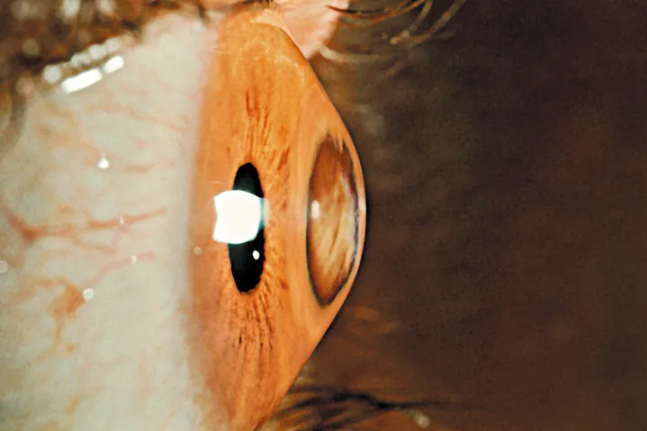

Ένας στους δέκα Έλληνες έχει κερατόκωνο, αλλά δεν το γνωρίζει

Η καθυστερημένη διάγνωση μπορεί να έχει σοβαρές συνέπειες, διότι στα τελικά στάδιά του ο κερατόκωνος συνήθως απαιτεί μεταμόσχευση κερατοειδούς για να αντιμετωπιστεί.